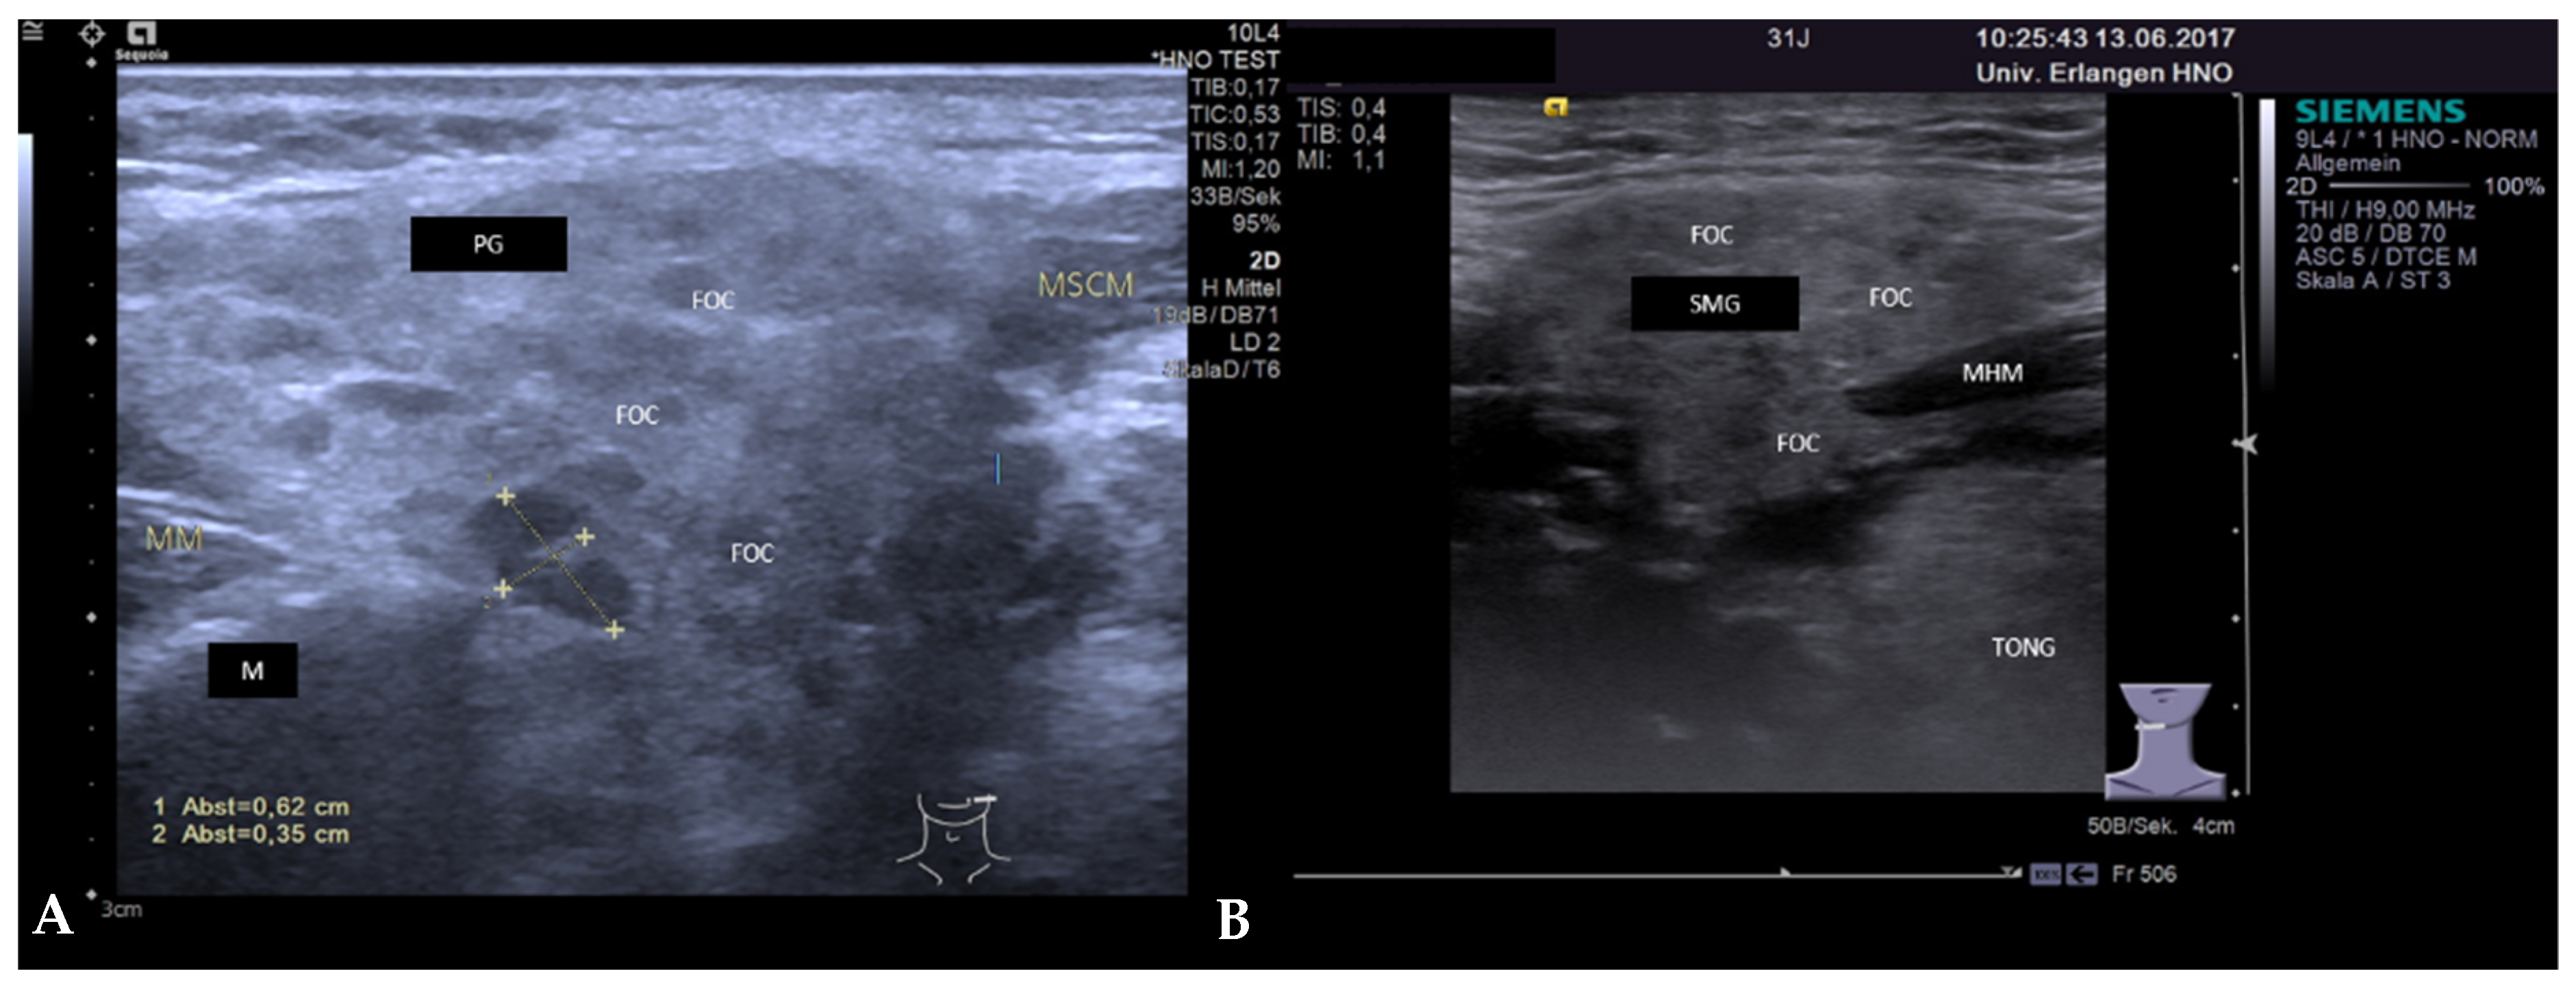

3.3.2. Obstructive Sialadenitis Caused by Sialolithiasis

3.3.3. Non-Sialolithiasis-Caused Unspecific Sialadenitis with Sialodochitis and/or Duct Stenosis with Primary or Secondary Obstruction